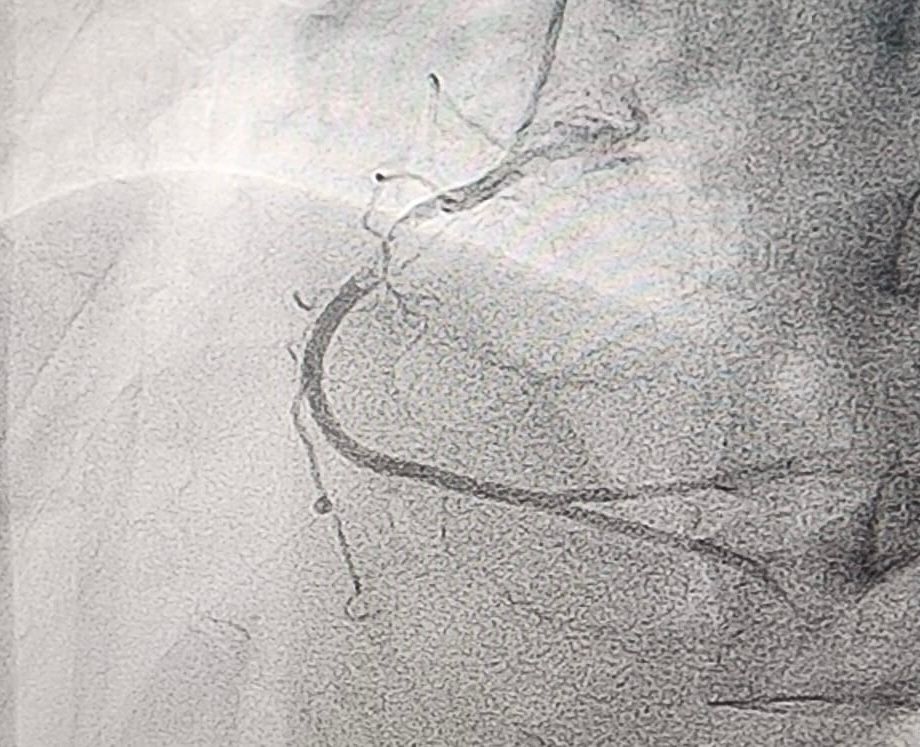

Coronary angiography revealed total occlusion of the proximal LCx and a sub totally occluded RCA with thrombus.

Both RCA and LCx were considered as the culprit lesion. We decided to addressed the lesion in RCA first, since the flow is still TIMI III. RCA was engaged with 6F JR guiding catheter. Run through wire was advanced distally to RCA. After pre dilatation with NC balloon 3.5 / 18 mm the thrombus disappeared. A 3.5 / 22 mm stent was implanted in RCA at 18 atm. Post dilatation with stent balloon at maximum pressure 20 atm. Final angiogram showed TIMI 3 flow. Then we intervene the LCx. We used BL guiding catheter to engage the LCx. Run through NS floppy wire was advanced to distal LCx. Coronary angiogram showed good contrast flow to distal LCx. Pre dilatation at proximal LCx with NC balloon 3.5 / 18 mm at 18 atm. DES was implanted at LCx at 20 atm. We did post dilatation at LCx with NC balloon up to 24 atm. Final angiogram showed TIMI III flow.